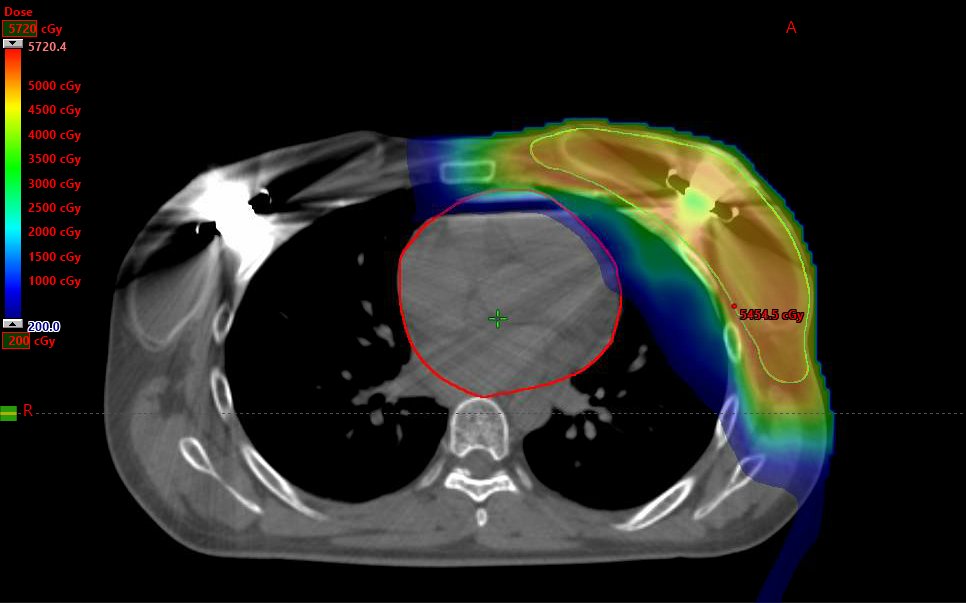

M. Bolton Showing you my cases since you think I don't treat breast. Here is a left sided PMRT with grossly involved IMNs and expanders - using IMPT with mean heart less than 1Gy while giving 63Gy to the grossly involved IMN node.

Here is a left sided PMRT with grossly involved IMNs and expanders - using IMPT with mean heart less than 1Gy while giving 63Gy to the grossly involved IMN node.